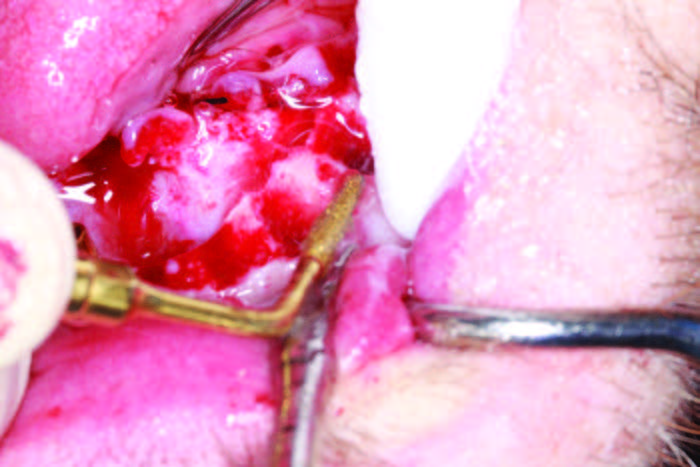

If the tooth is ankylosed or multi-rooted, then a Piezo surgical device is used to sever the periodontal ligaments (Figure 4c). It uses micro vibrations to allow the various inserts to remove bone, cut ligaments, and level osteotomies with a minimum of bleeding. It practically stops bleeding due to the movement of bone, the sealing of capillaries, and saline irrigation during the procedure. Extractions of all the mandibular teeth were done, and a caliper was used as measured in the reformatted CBCT scan (3DDX) to mark the alveolus and begin osteoplasty at each socket for the planned implant platform placement (Figure 5a). The osteoplasty was performed atraumatically using the Piezosurgery unit, and, after a cut was made buccal to lingual, a diamond insert was used to smooth all sharp edges and to level the implant sites using the Piezo surgical device (Figures 5b and 5c). A 10,600-nm CO2 laser (LightScalpel) was used to disinfect the sockets (Figure 6a). The laser uses water as its main chromophore and removes tissue by vaporization while limiting any zone of necrosis. Bacterial kill within the extraction socket, granuloma removal, and hemostasis are all accomplished with the use of this true spatially accurate laser device. In fact, use of the laser to trim tissue around abutments and permucosal healing abutments, treat peri-implantitis, and remove frena to decrease tissue pull on implants are all indicated procedures for this wavelength of CO2 laser.[3] Trimming of hypertrophic tissue during maxillary provisional placement allows for tissue modification without bleeding (Figure 6b).